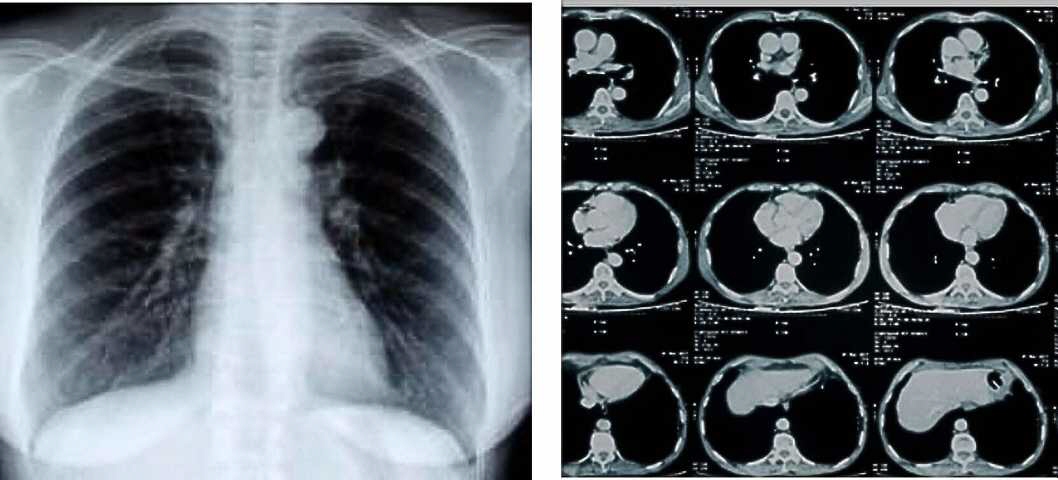

Chest X-ray / CT Scan